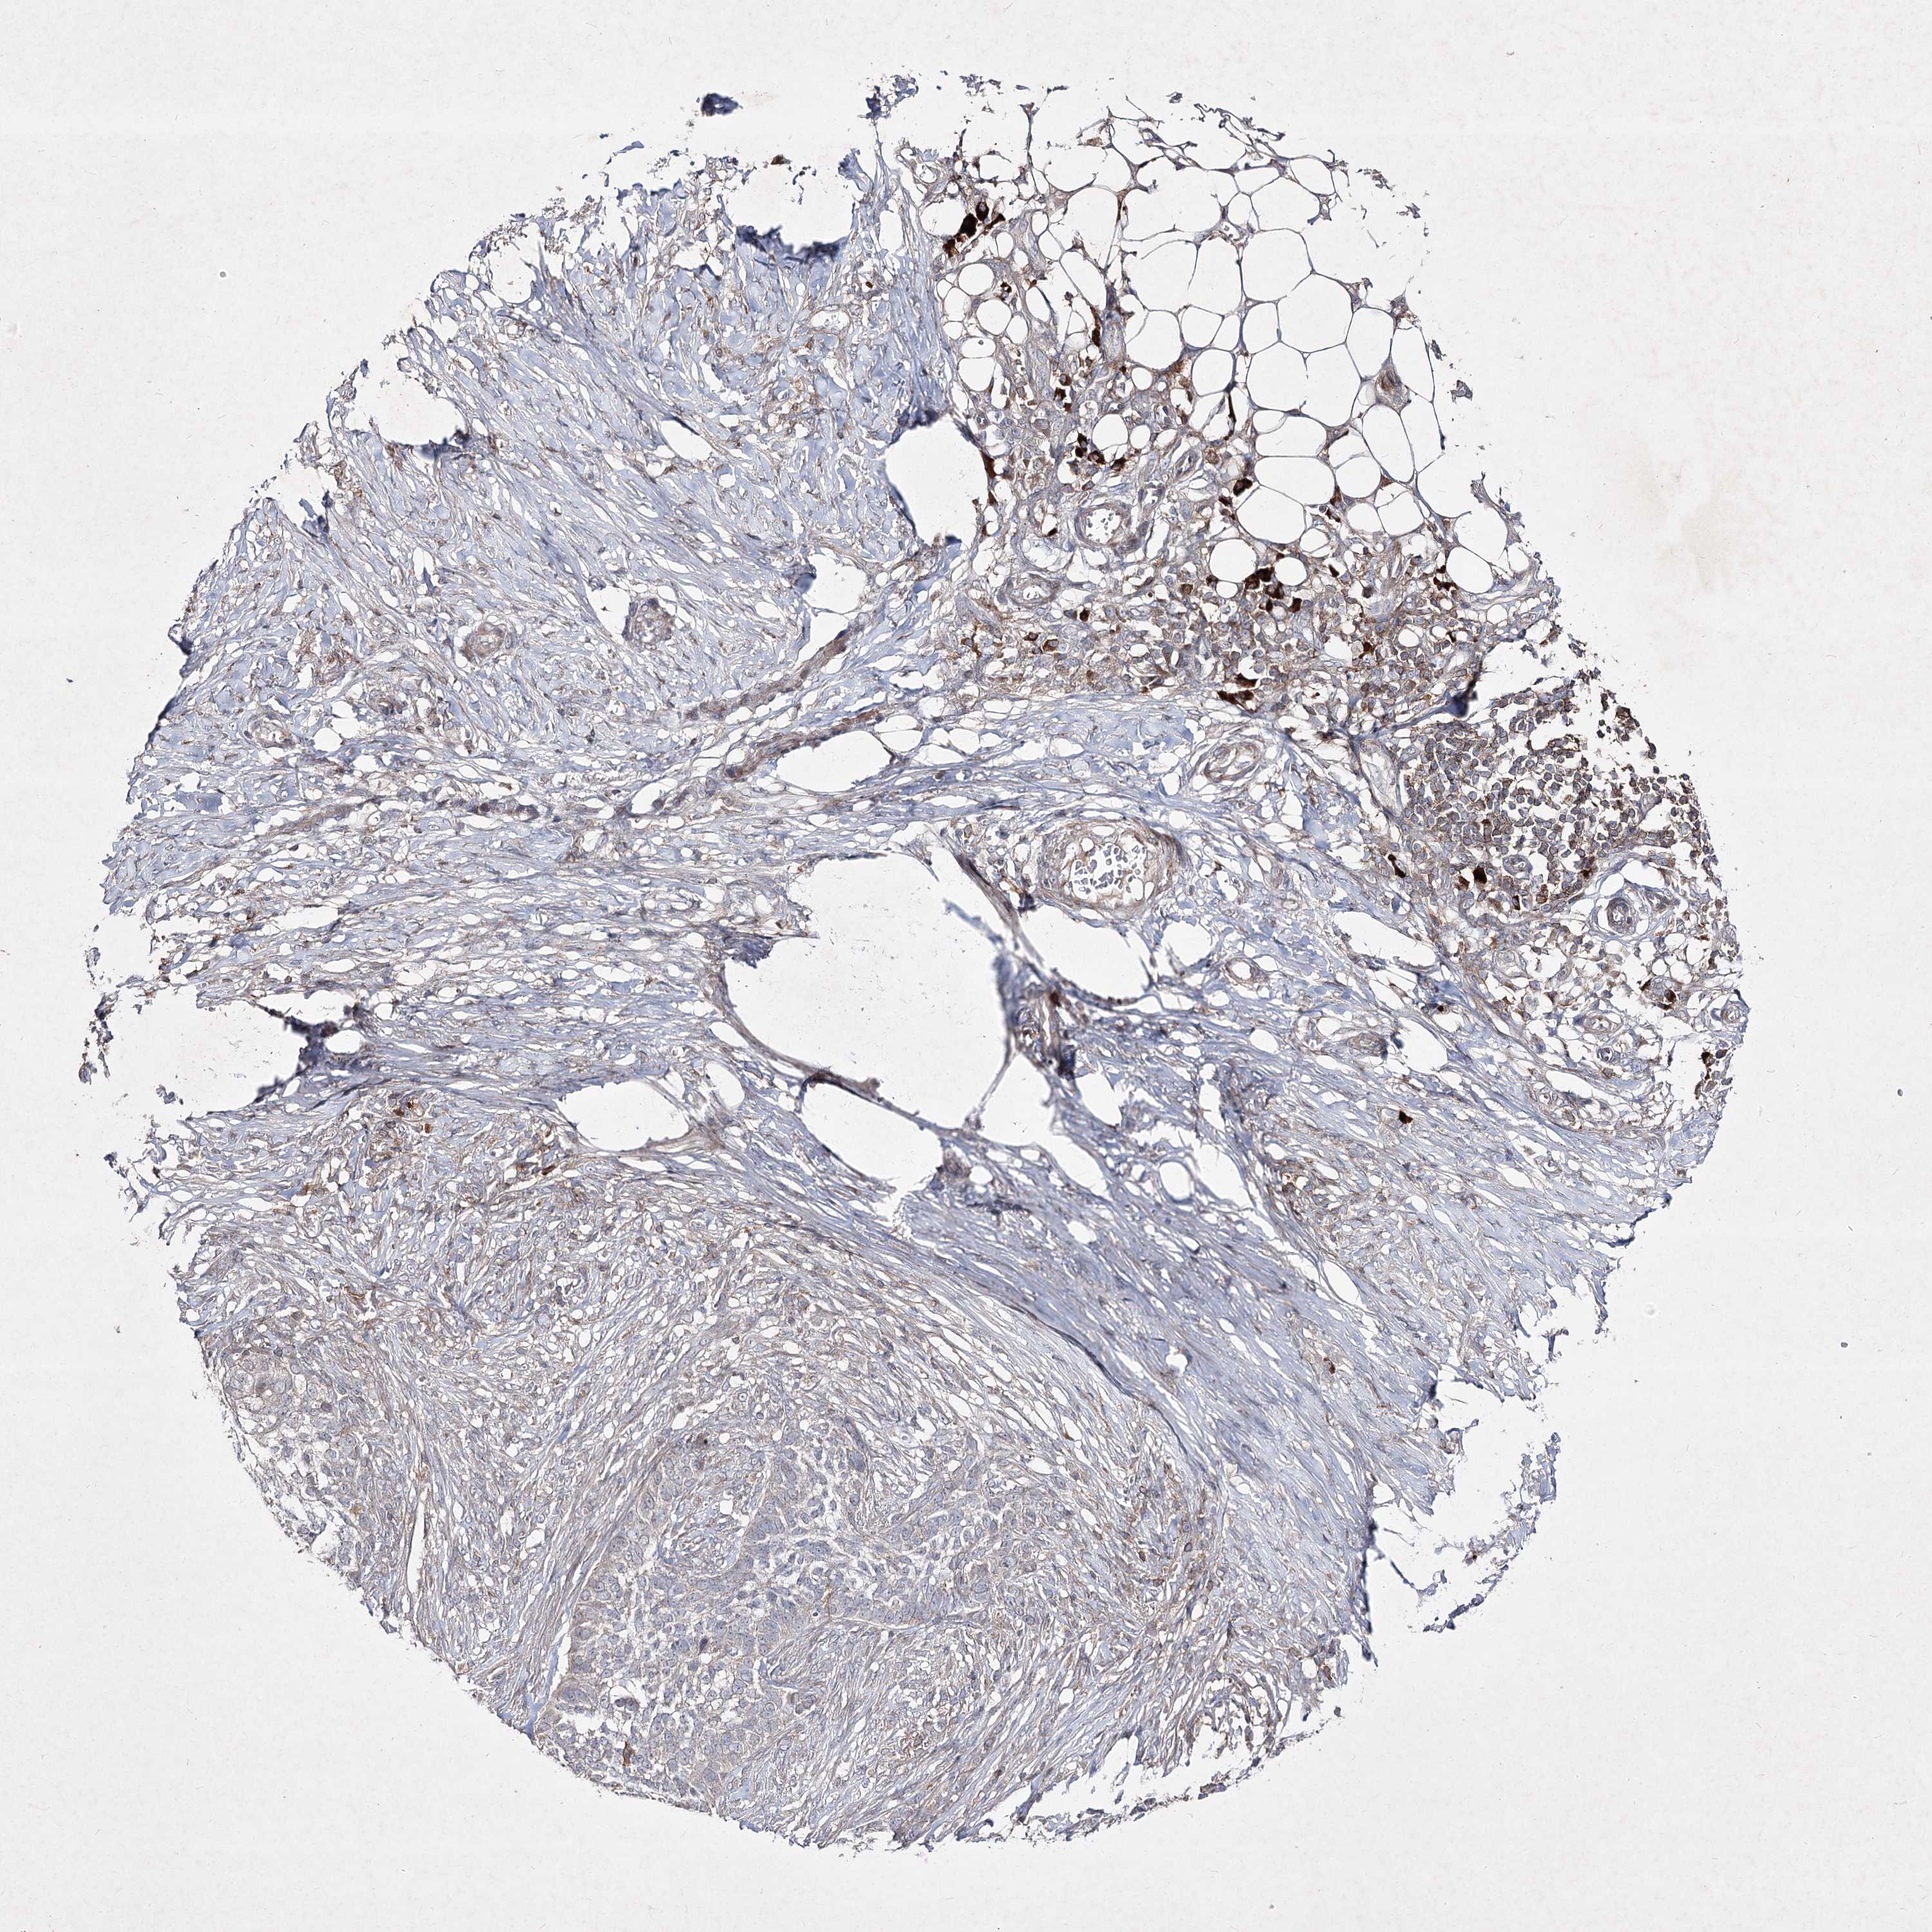

SKIN CANCER - Protein expressioni

A mouse-over function shows sample information and annotation data. Click on an image to view it in a full screen mode. Samples can be filtered based on level of antibody staining by selecting one or several of the following categories: high, medium, low and not detected. The assay and annotation is described here.

Antibody stainingi

Antibody staining in the annotated cell types in the current human tissue is reported as not detected, low, medium, or high, based on conventional immunohistochemistry profiling in selected tissues. This score is based on the combination of the staining intensity and fraction of stained cells.

Each image is clickable and will lead to virtual microscopy that enables deeper exploration of all samples and also displays staining intensity scores, fraction scores and subcellular localization as well as patient and tissue information for each sample.

Antibody HPA036697

Staining

High

Medium

Low

Not detected

Intensity

Strong

Moderate

Weak

Negative

Quantity

>75%

75%-25%

<25%

None

Location

Nuclear

Cytoplasmic/membranous

Cytoplasmic/membranous,nuclear

Basal cell carcinoma

Squamous cell carcinoma, NOS

Squamous cell carcinoma, metastatic, NOS